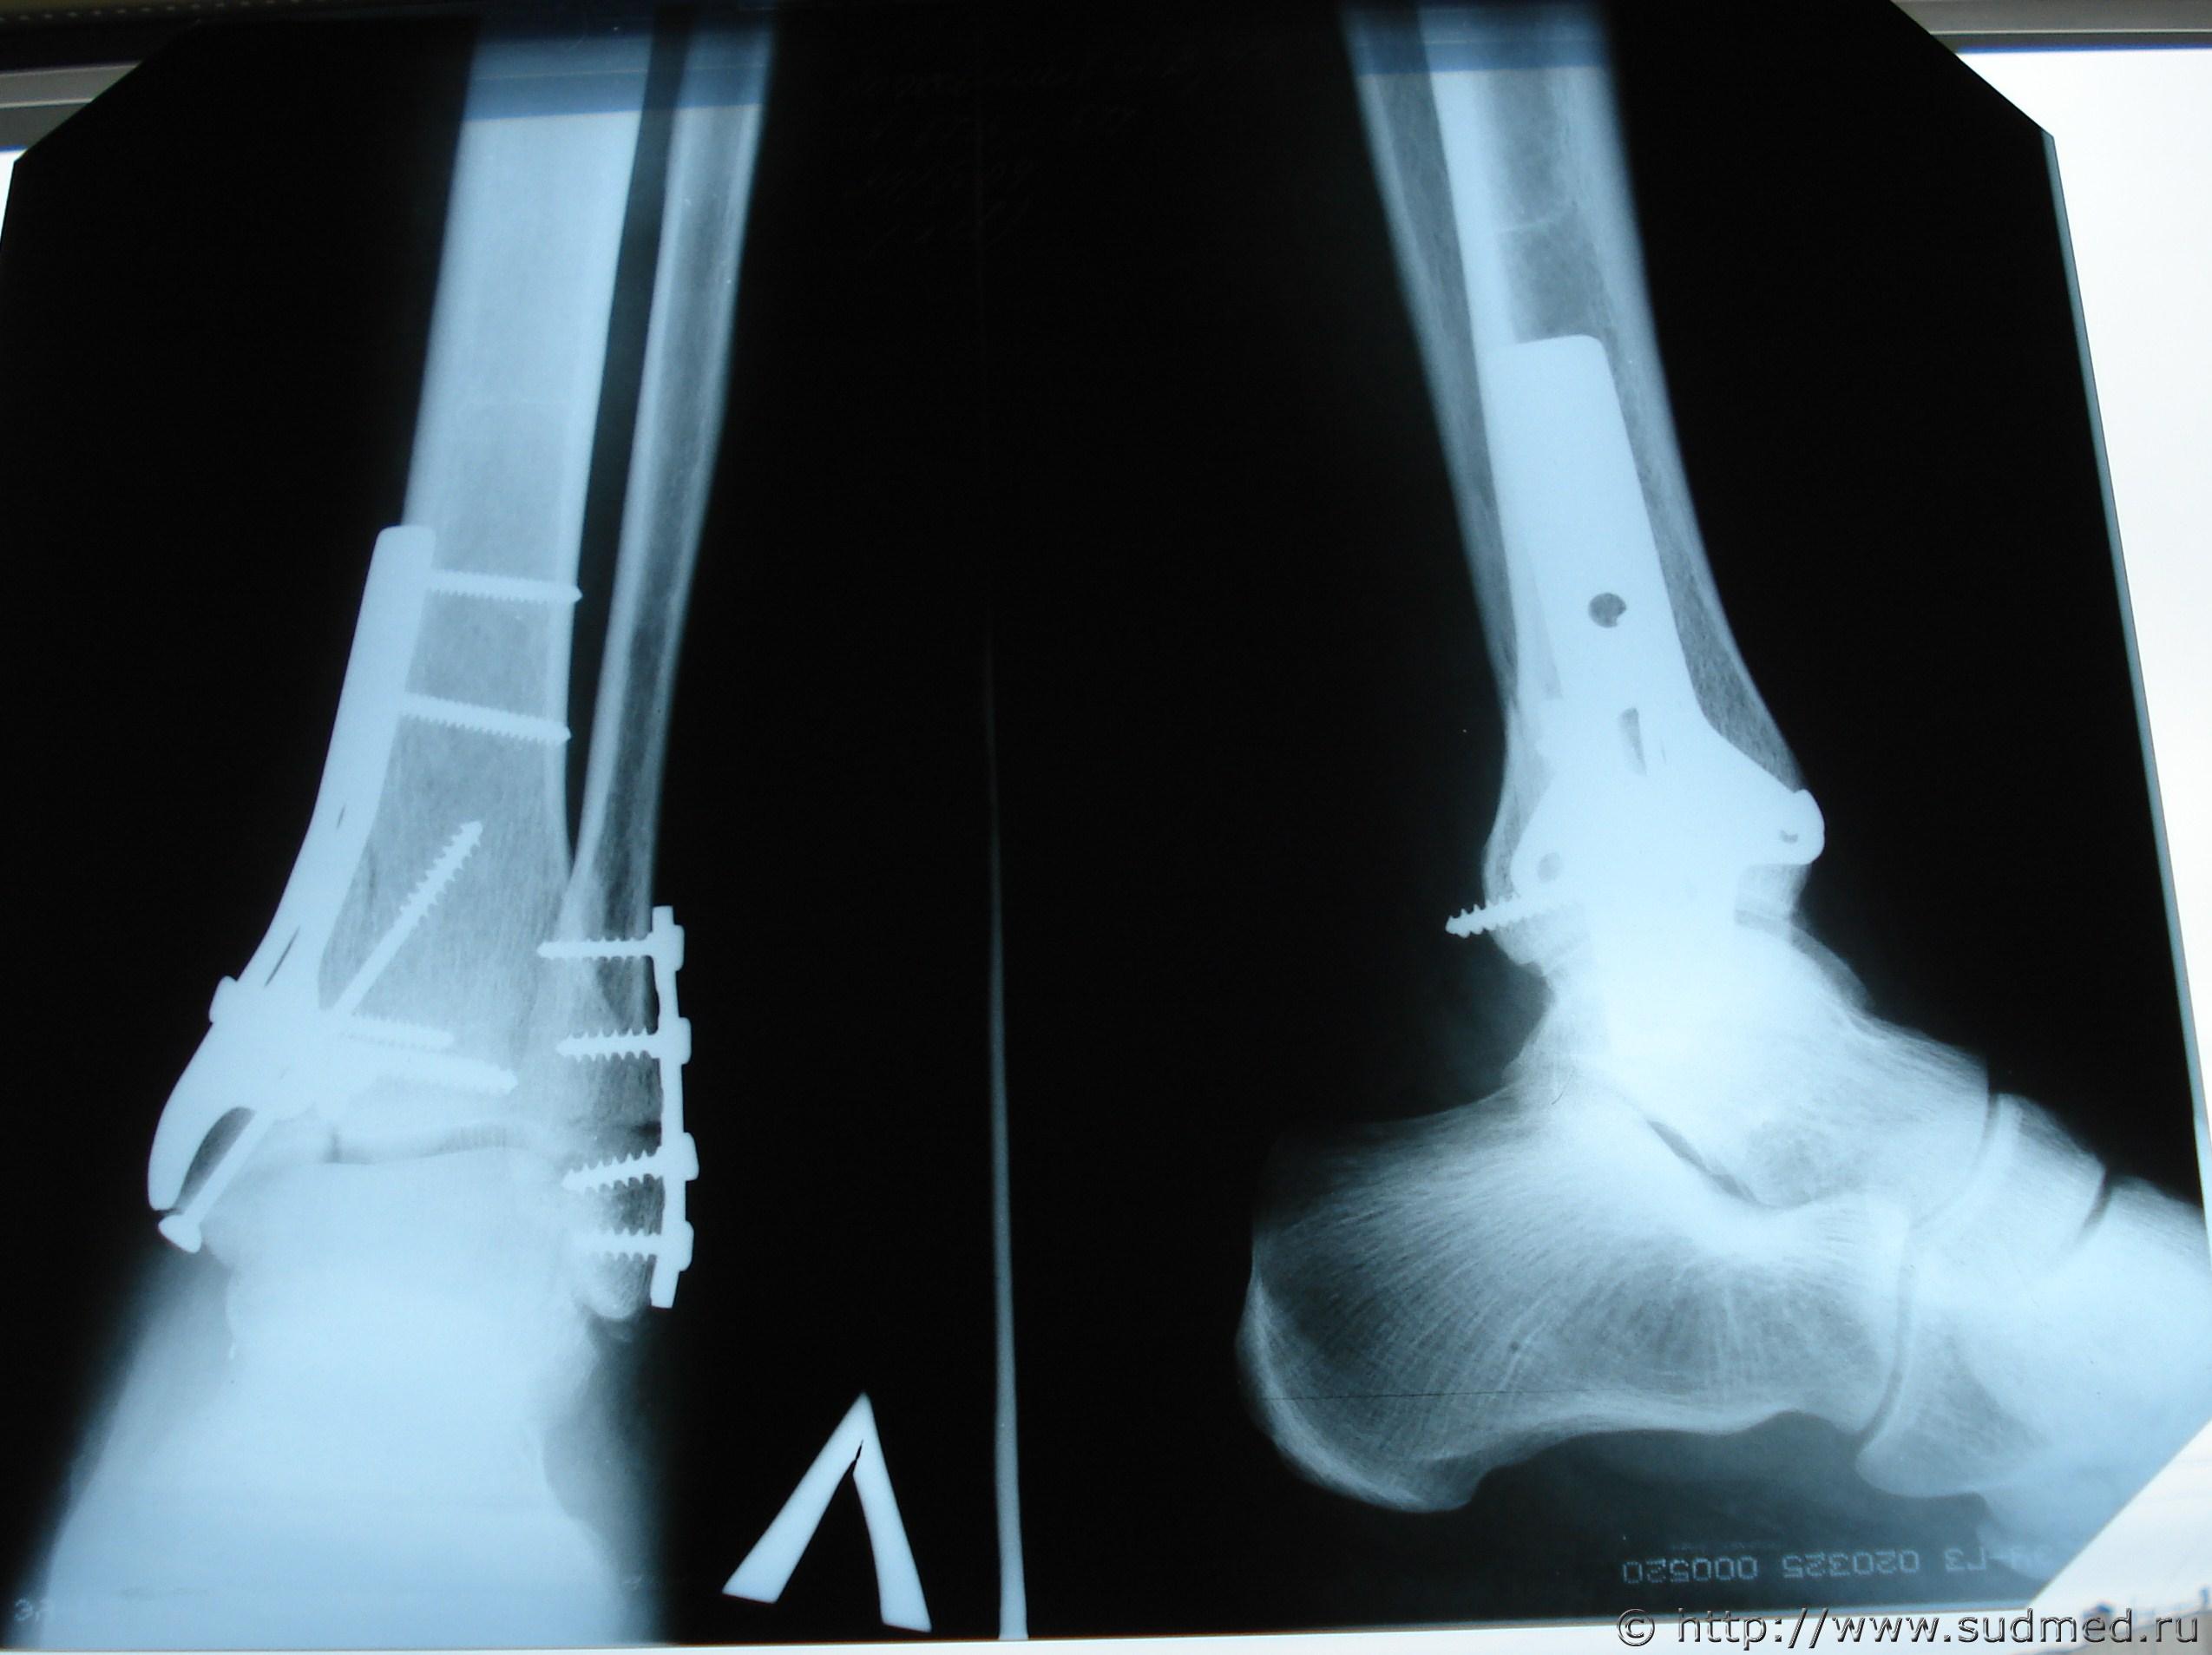

«Диагноз: Оскольчатый компрессионный внутрисуставной перелом дистального метаэпифиза с переходом на диафиз, заднего края б/берцовой кости, наружной лодыжки левой голени с подвывихом стопы кнаружи и кзади. Перелом 5 плюсневой кости левой стопы.

.. выполнена операция: открытая репозиция перелома, остеосинтез больше берцовой кости пластиной «кленовый лист» и винтами, остеосинтез наружной лодыжки реконструктивной пластиной пластиной и винтами».

В Вашем случае ситуация спорная, т.к. не совсем понятна формулировка "перелом дистального метаэпифиза с переходом на диафиз". Формально - если дистального метаэпифиза, то средний, если все же диафиза - то тяжкий возможен. Без изучения снимков ответ по тяжести вреда дать невозможно, и даже с ними оценка разных экспертов в отношении места перелома может разниться.

Попробовал сделать копию снимка. Посмотрите, пожалуйста.

И еще одна копия снимка.. Может быть она получше получилась.

На снимках, мне кажется, видно, что перелом имеет место не только метаэпифиза (хряща), но и диафиза (тела большеберцовой кости), иначе её оперировавший врач не крепил бы металлической пластиной.

Извините, уважаемые эксперты, что представлен послеоперационный снимок (через 10 дней после травмы проведена операция). Остальная часть снимков находится в деле.

Все переломы в пределах эпифиза и метэпифиза. Достоверных данных о переломе диафиза не усматриваю.

Согласен с уважаемым коллегой FILINом - переломы не переходят на диафиз. Значит, вред здоровью средней тяжести был выставлен правомерно.

3. Представлены рентгенограммы левого голеностопного сустава в двух проекциях (3) №№ 117, 118, 279 от 13.04.2009г. и 15.04.2009г. на имя К......, 43 лет, - рентгенологическая картина соответствует описанию указанных рентгенограмм в медицинских документах.

Снимки с полным охватом поврежденной области, хорошего качества, в двух основных проекциях. Для вывода о степени вреда здоровью достаточно и одного такого снимка.